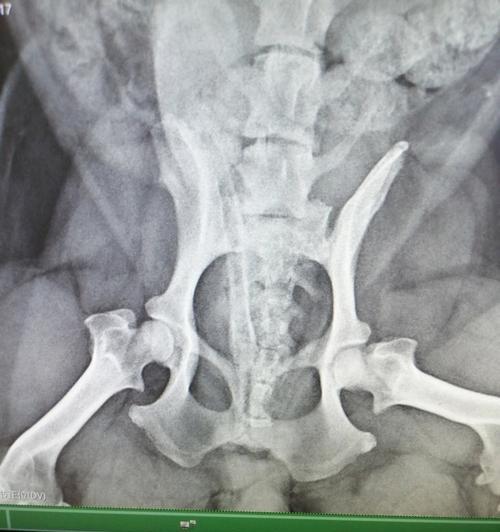

-腿髋坏死,也称为股骨头坏死,是一种骨骼疾病,常见于中小型犬。

-腿髋坏死的主要原因是血液供应不足导致股骨头缺血坏死。

-配合兽医进行X光检查等诊断方法,以确诊腿髋坏死。